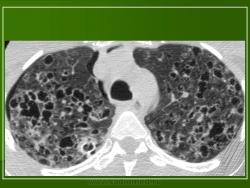

В 5 наблюдениях (21%) из больных с распространенной формой заболевания отмечались изменения в легких в виде обогащения, избыточности легочного рисунка, его деформации по сетчато-петлистому типу, очаговых теней. Корневая и медиастинальная аденопатия отсутствовали. В 1 случае в легких выявлена киста, которая периодически осложнялась нагноением (Рис. 4).

Поражение легочной ткани (рис. 22) свойственно любому возрасту. Часто больные имеют общие симптомы — лихорадку, слабость, реже — кашель, одышку, боли в грудной клетке. На рентгенограммах отмечается деформация и усиление легочного рисунка и микроузловые инфильтративные тени. Поражение костного мозга (с наличием клеток Лангерганса) сопровождается цитопенией периферической крови.

Рис. 22. Поражение легких при Лангер-гансово-клеточном гистиоцитозе.